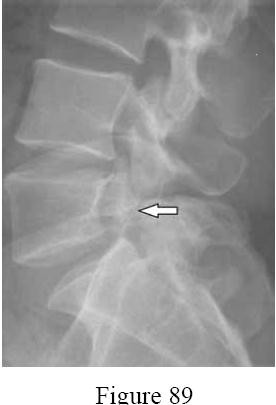

Question 27

A 25-year-old male suffers a stab wound to the thoracic spine. Neurological examination reveals loss of motor function and proprioception in the right lower extremity, and loss of pain and temperature sensation in the left lower extremity. This presentation implies injury to which of the following combinations of spinal cord tracts?

Explanation

Question 28

A 14-year-old gymnast presents with chronic low back pain. Conservative management for 6 months has failed.

Radiographs demonstrate a Grade II isthmic spondylolisthesis at L5-S1. What is the recommended surgical treatment?